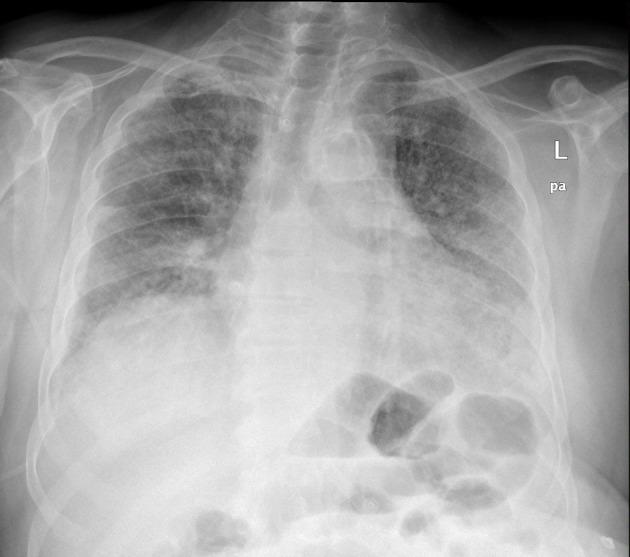

Immune checkpoint inhibitors like pembrolizumab represent a modern approach to the management of various malignancies, including non-small cell lung cancer. The therapeutic activity of immunotherapy is exerted by the activation of immune cells against the tumor cells. However, systemic activation of the immune system can lead to the development of autoimmune complications known as immune-related adverse events. A combination of rare immune-related adverse events is occasionally observed simultaneously in the same patient. We present the case of a 66-year-old male with squamous non-small cell lung carcinoma who presented to the emergency department with dyspnea and respiratory failure. Imaging findings were consistent with pulmonary embolism and nonspecific interstitial pneumonitis. One month before this event, he was diagnosed with bullous pemphigoid following 21 cycles of treatment with pembrolizumab. The radiological findings, the lack of response to antibiotics, the negative microbiological workup, and the excellent response to corticosteroids established the diagnosis of pembrolizumab-induced pneumonitis. The combination of bullous pemphigoid and pneumonitis secondary to pembrolizumab is rare; only a few case reports exist in the literature. Hence, this case highlights the possibility of multiple immune-related adverse events in the same patient. The exclusion of infectious diseases and other immunologic disorders with a similar clinical presentation is necessary to make the final diagnosis of immune-related adverse events and start the appropriate treatment. Serology, histopathology, and direct immunofluorescence aid to the diagnosis of immune-related bullous pemphigoid; the differential diagnosis includes other pemphigoid or lichenoid diseases, Stevens-Johnson syndrome/toxic epidermal necrolysis, and drug reaction with eosinophilia and systemic symptoms. Imaging, microbiological testing, and bronchoscopy (if possible) confirm the diagnosis of immune-related pneumonitis, which should be differentiated from acute coronary syndrome, cardiogenic pulmonary edema, pulmonary embolism, tumor progression, and lower respiratory tract infections (especially pneumonia in immunocompromised patients). An interdisciplinary approach is necessary for the management of these cases.

像派姆单抗这样的免疫检查点抑制剂代表了一种治疗包括非小细胞肺癌在内的各种恶性肿瘤的现代方法。免疫疗法的治疗活性是通过激活免疫细胞对抗肿瘤细胞来发挥作用的。然而,免疫系统的全身激活可导致被称为免疫相关不良事件的自身免疫并发症的发生。在同一患者中偶尔会同时观察到罕见的免疫相关不良事件的组合。我们报告一例66岁男性鳞状非小细胞肺癌患者,他因呼吸困难和呼吸衰竭就诊于急诊科。影像学检查结果与肺栓塞和非特异性间质性肺炎相符。在此事件发生前一个月,他在接受21个周期的派姆单抗治疗后被诊断为大疱性类天疱疮。影像学检查结果、对抗生素无反应、微生物学检查阴性以及对皮质类固醇的良好反应确立了派姆单抗诱发肺炎的诊断。派姆单抗继发大疱性类天疱疮和肺炎的组合很罕见;文献中仅有少数病例报告。因此,该病例凸显了同一患者发生多种免疫相关不良事件的可能性。为了最终诊断免疫相关不良事件并开始适当治疗,有必要排除具有相似临床表现的感染性疾病和其他免疫性疾病。血清学、组织病理学和直接免疫荧光有助于免疫相关大疱性类天疱疮的诊断;鉴别诊断包括其他类天疱疮或苔藓样疾病、史蒂文斯 - 约翰逊综合征/中毒性表皮坏死松解症以及伴有嗜酸性粒细胞增多和全身症状的药物反应。影像学检查、微生物学检测和支气管镜检查(如果可能)可确诊免疫相关肺炎,应将其与急性冠脉综合征、心源性肺水肿、肺栓塞、肿瘤进展以及下呼吸道感染(尤其是免疫功能低下患者的肺炎)相鉴别。对于这些病例的管理,采用多学科方法是必要的。